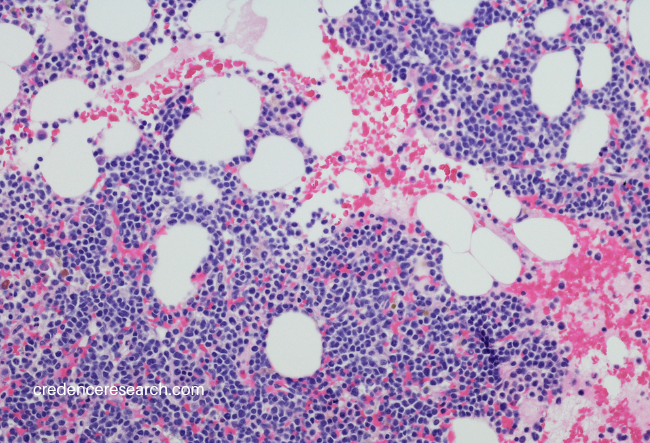

The term "High Grade Neuroendocrine Neoplasms Market" refers to the market for medical treatments, therapies, and related products and services that are specifically focused on high-grade neuroendocrine neoplasms (NENs). High-grade neuroendocrine neoplasms (NENs) are a group of rare and aggressive cancers that originate in neuroendocrine cells. These cells are found throughout the body, particularly in organs like the pancreas, lungs, gastrointestinal tract, and other endocrine glands. Neuroendocrine cells release hormones into the bloodstream and play a role in regulating various bodily functions.

High-grade NENs are characterized by their rapid growth and tendency to metastasize (spread to other parts of the body). They are considered more aggressive and have a poorer prognosis compared to low-grade NENs. These tumors are often classified as neuroendocrine carcinomas and can be further categorized based on their tissue of origin, such as small cell or large cell neuroendocrine carcinoma.